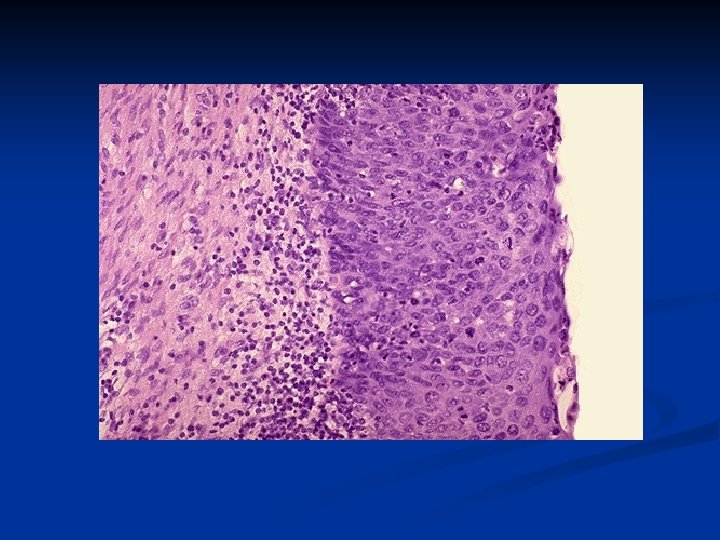

CIN III (carcinoma in situ) with diffuse atypia and loss of maturation. Downloaded from: Robbins & Cotran Pathologic Basis of Disease (on 24 February 2006 08: 56 AM) © 2005 Elsevier

Carcinoma insitu